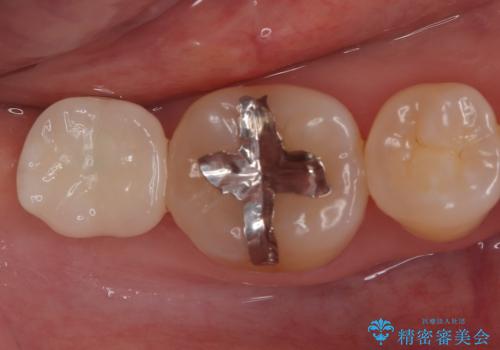

今回はスクリューリテインにて修復を行なっています。